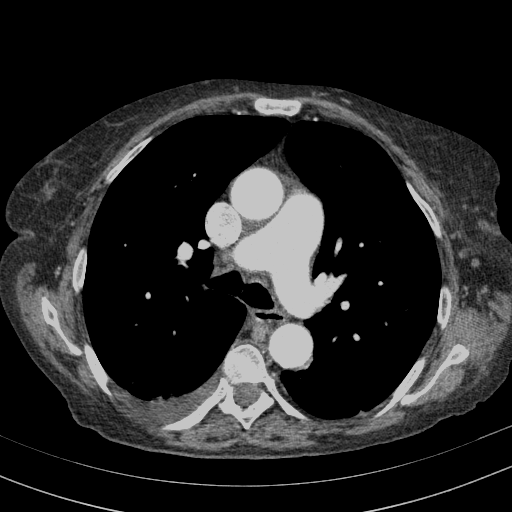

Targeted Slice 70 - Mediastinum Window Analysis (Generated vs Real Venous)

0.629

Mediastinum SSIM

49.0

Mediastinum RMSE

22.4

Mediastinum MAE

Average Mediastinum Window Metrics Across All Slices (153 slices) - Generated vs Real Venous

0.549

Mediastinum SSIM (Avg)

54.0

Mediastinum RMSE (Avg)

28.3

Mediastinum MAE (Avg)

Original VENOUS CT scan

Full window (WL 1023.5, WW 4095 β†’ Low βˆ’1024, High +3071)

Mediastinum window (WL 40, WW 400 β†’ Low βˆ’160, High +240)